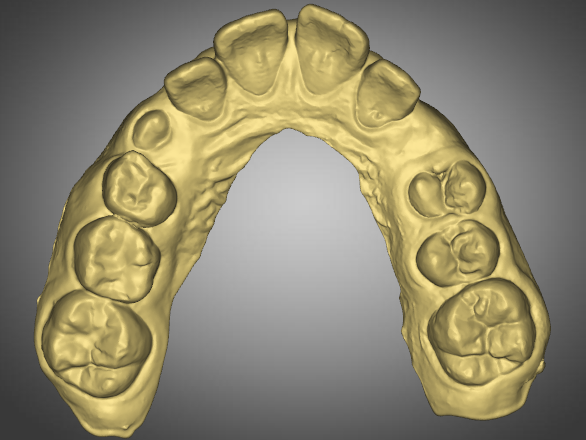

Pre-Op Analysis – 2020-11-25

- Mixed Dentition

- Aligners – Started 2021-05 and kept in place to maintain space of the unerupted premolars

- Yellow Stone Model = Pre-Op at 2020

- Blue Overlay = Progress scan at 2022-07-04 after about 12 months of Mybrace K1 which came after 6 months in aligners.